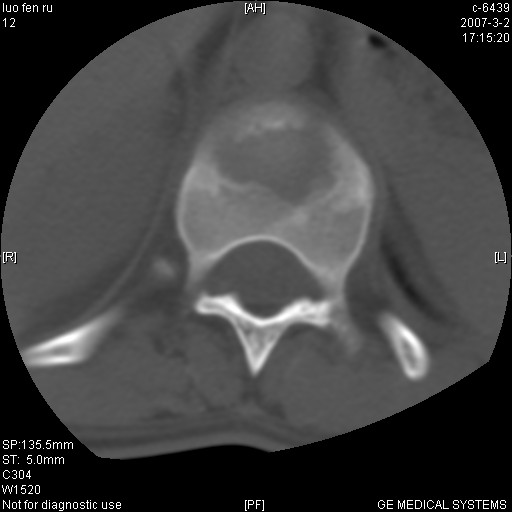

标题: CT6952:T11椎体病变请讨论

女,19岁.背部疼痛一月余.自诉幼时有个外伤史.

腰椎平片示,t11椎体呈楔形改变,椎间隙未见异常.

当是应是椎体(前半部较厉害)压缩性骨折,这就印证了这就是陈旧性骨折。

病人病史不长,病变表现比较明显,如果是结核,病史不支持,椎间隙不窄,临近椎体正常,椎旁无冷浓疡,但从病变本身硬化也较多,均不太支持结核。慎重考虑的话,可以问一下病人有无结核病史。如果没有,更多的应该考虑陈旧性骨折,伴有慢性椎间盘炎可能。确诊后记着告知啊!

结核:好发于胸椎,其次为腰椎,相邻椎体受侵,椎间隙变窄,椎体变扁,椎旁或腰大肌冷脓肿形成。

t11椎体前缘不规则形骨质破坏,周围有硬化边,软组织肿块不明显,首先考虑:骨嗜酸性肉芽肿 。期待随访结果。